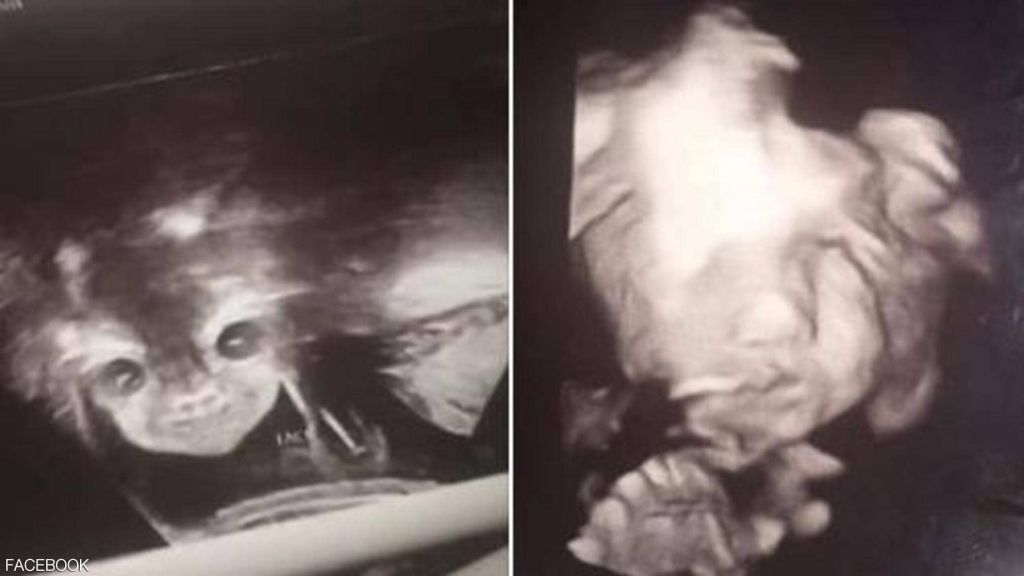

فوجئ أبوان بصورة بدت مخيفة لطفلهما المنتظر وهو في بطن أمه، خلال جلسة في معمل الموجات فوق الصوتية للاطمئنان على حالته.

وأثارت صورة “الجنين الشيطان” حسب تعبير الأم، التي انتشرت بشكل واسع على مواقع التواصل الاجتماعي، ضجة كبيرة حول العالم، فضلا عن قلق والديه.

ونشرت الأم المراهقة التي تدعى إيانا ألستون (17 عاما)، الصورتين اللتان التقطتا لجنينها، على حسابها في “فيسبوك”، وعلقت عليها بالقول: “معظم الأطفال يختبئون من الكاميرا. انظروا إلى طفلتي الشيطانية”.

وأضافت: “كانت تبدو عادية، لكن عندما علمنا أننا سنرزق بفتاة، وتم وضع الجهاز على بطني مرة أخرى، فتحت عينيها وابتسمت. أحب هذه الطفلة الشيطانية جدا”.

وأشارت المراهقة إلى أن الطبيبة التي كانت معها خلال جلسة التصوير بـالموجات فوق الصوتية، أخبرتها أن طفلتها طبيعية وبحالة جيدة، لافتة إلى أنه من غير الغريب أن يظهر الجنين بهذا الشكل في الصور.